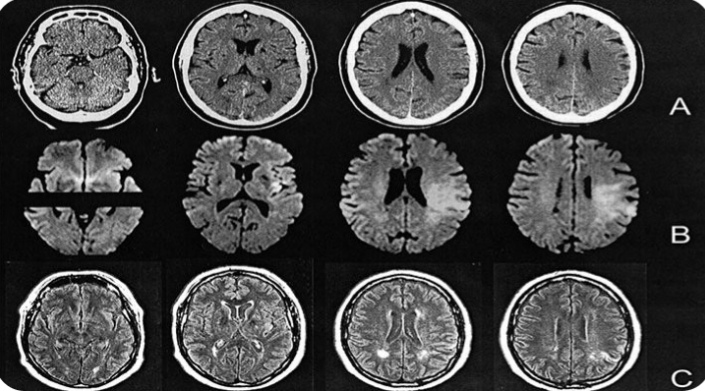

تمكن علماء من فك لغز “النقاط الساخنة” الغامضة الموجودة على سطح خلايا الدماغ، والتي كان وجودها يشكل محورا محيرا للعلماء على مدار عقود مضت.

وكان الدور الذي تلعبه مجموعات معينة من البروتينات الموجودة على سطح خلايا الدماغ، وبالتحديد على الجزء الذي يلعب دورًا رئيسيًا في التعلم والذاكرة، محيرًا للعلماء، لكن هذا اللغز البيولوجي تم حله أخيرًا، وفق ما ذكر موقع “سيانس أليرت”.

وكان معروفًا أن تعطيل هذه النقاط يمكن أن يؤدي إلى اضطرابات عصبية شديدة، لكن لم يتضح سبب ذلك، إلى أن وجدت دراسة جديدة إلى أن المجموعات هي “نقاط ساخنة” لإشارات الكالسيوم، وهي حيوية في تنشيط التعبير الجيني.